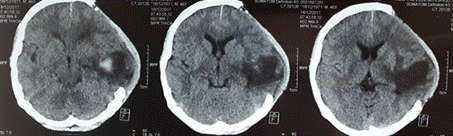

En las figuras 1, 2 y 3 se presentan neuroimágenes realizadas al paciente. (Figura 1)(Figura 2)(Figura 3)

Figura 2 Resultados de una Tomografía Axial computarizada en la que se observa estigmas de craniectomía temporo-parietal izquierda. Engrosamiento membranoso dural. Edema cerebral con efecto de masa aún en el área temporo-parietal con compresión ventricular y desplazamiento de los marcadores de la línea media.